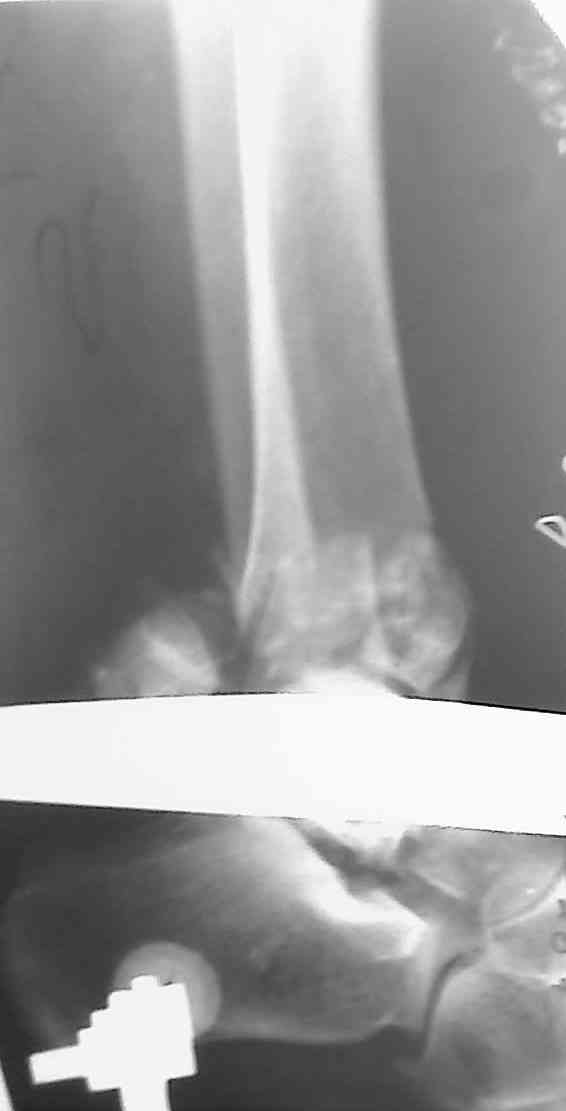

Добавлены КТ снимки. Прошу прощения за качество.

С уважением, Коваленко А.Н.

Снова приветствую вас, коллеги. К моменту вступления в обсуждение аксакалов, операция была, увы, выполнена(31.10.07.) Начали с доступа к наружной лодыжке, произвели ее фиксацию спицами, развернули кусок заднего края, наложили дистрактор, затем произвели дистракцию, фиксацию спицами дистального эпиметафиза б/бк,Рентгено-контроль. синтез наружной лодыжки 1/3пластиной. из двух коротких разрезов сформирован канал под медиальную тибиальную пластину LCP. Края ран ушиты без натяжения. Прочувствовать жесткость фиксации винтами с угловой стабильностью не удалось, поэтому дистрактор оставлен на энное время.

На представленных R-снимках не окончательный вид после остеосинтеза. Дистальная опора давила на стопу, пришлось ее сместить проксимально, в рез-те чего, она закрыла щель сустава, последние снимки не информативны.

Честно признаться тяжело на душе после такой операции,-было всё хорошо после первоначальной дистракции, хорошая редукция отломков, после остеосинтеза пластинами появилась подвывых стопы кнаружу, от пластини LCP никакой толку-дистальные винты в зоне излома и дистальный отломок не охвачен, проксимально всего один винт, дистальные винты из м/б кости проходят сквоз сустава и упирается в таранку, стопа в эквинусном положении.Если даже всё обойдется, этот сустав нормально не будет работат.